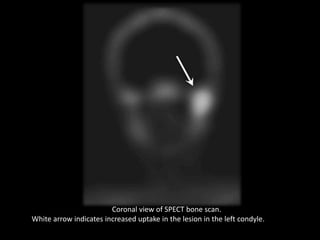

Coronal view of SPECT bone scan.

White arrow indicates increased uptake in the lesion in the left condyle.